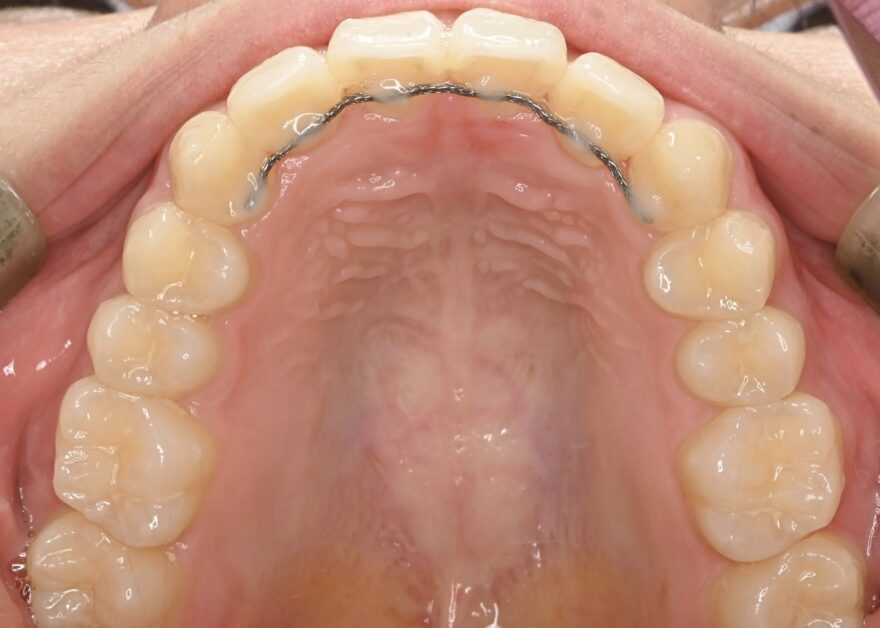

治療後の口腔内写真

約2年の動的期間(歯を動かす時期)で、ここまで整った歯並びになりました。

八重歯が完全に治りました。

前歯には後戻りを防止するための保定装置を装着しています。

下顎の前歯にもワイヤーによる保定装置を装着しています。